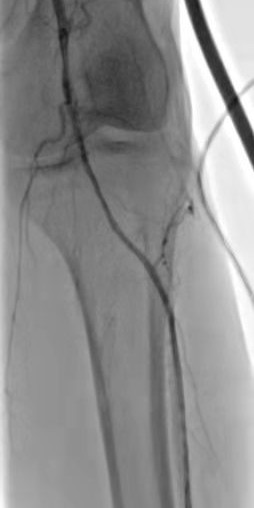

術(shù)中DSA:箭頭提示雙髂動(dòng)脈血栓栓塞,血流中斷

術(shù)中DSA:雙髂動(dòng)脈血流恢復(fù)

箭頭所示:右腘動(dòng)脈血栓栓塞,血流中斷

術(shù)后右下肢動(dòng)脈血流復(fù)通

箭頭所示:左股、腘動(dòng)脈血栓栓塞,血流中斷

術(shù)后:左股腘動(dòng)脈血流復(fù)通